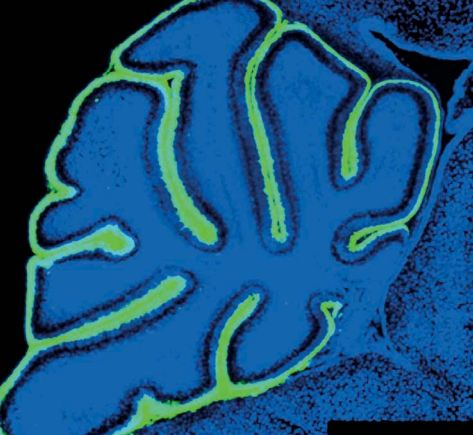

Когда мозг разделяется на области, клетки-предшественники, или стволовые клетки, начинают разрастаться и делиться на нейроны и глиальные клетки — функциональные элементы взрослого мозга. Эти клетки необходимы для успешного развития мозга и различаются в зависимости от вида и области мозга, в которой находятся.Клетки «внешней» радиальной глии, вероятно, сыграли важную роль в разрастании коры больших полушарий, что характерно для эволюции человека.Глиальные клетки помогают новым нервным клеткам продвигаться вдоль своих отростков, создавая «строительные леса», которые позволяют нервным клеткам достичь цели.Важность нервных стволовых клеток подтверждается тем, что их повреждение ведёт к различным порокам развития, например, к микроцефалии (слишком маленький головной мозг) и лиссэнцефалии (гладкий головной мозг без извилин).Клетки «внешней» радиальной глии есть у приматов, но особенно хорошо развиты у человека. Эти клетки участвовали в разрастании коры головного мозга, что повлияло на эволюцию вида.Клетки радиальной глии направляют нейроны при их миграции в кору и активно делятся, давая начало как нейронам, так и «настоящим» глиальным клеткам.Мозжечок — структура мозга, которая содержит больше нейронов, чем весь остальной мозг вместе взятый. Стволовые клетки мозжечка — одна из самых активных групп клеток головного мозга: они генерируют огромное количество нейронов, которые называют мозжечковыми гранулярными нейронами.